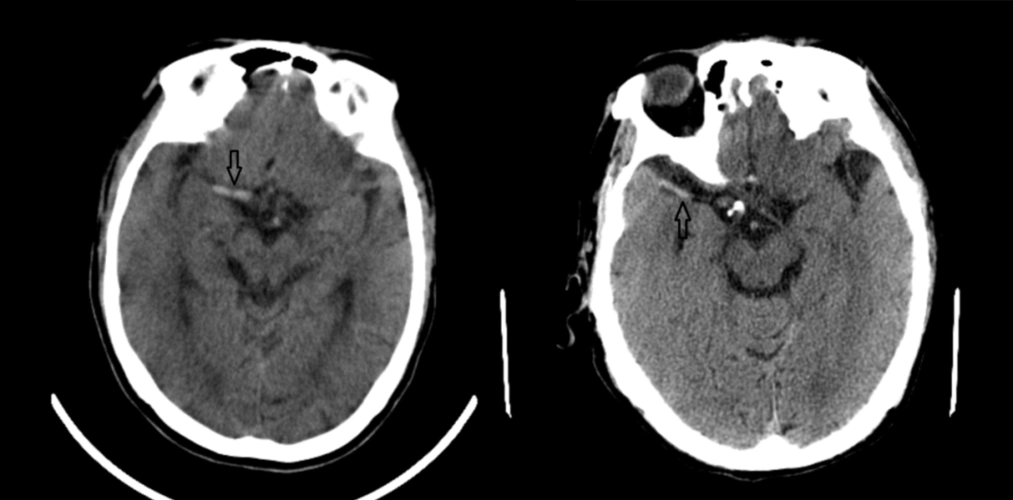

67超急性期大面积脑梗死ct平扫表现

通过ct平扫和核磁t2及flair像,均发现病灶显示不是很明显,容易造成漏

▎头颅ct平扫有高血压病史10年,最高血压190/100mmhg,目前口服药物